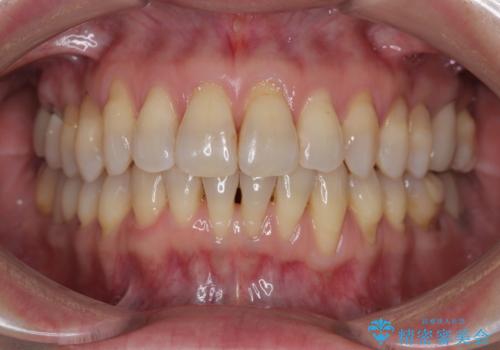

内側に転位した歯とボロボロのむし歯 インビザラインによる矯正治療とむし歯治療

- ボロボロのむし歯とデコボコの歯列を気にして来院された患者様です。

ボロボロとなっていた歯は抜歯が必要な状態でしたが、舌側転位している歯を移動させることで抜歯スペースを埋めることができるため、矯正治療により歯列を整えることとしました。

舌側転位の改善にインビザラインを用いるのはやや難易度が高くなりますが、前歯部のデコボコは軽度であったため、インビザラインによる矯正治療を行うこととしました。

矯正治療開始時に、インビザライン矯正の加速装置を購入されましたが、インビザライン自体をあまりしっかりと使用できず、4年間の治療期間となりました。